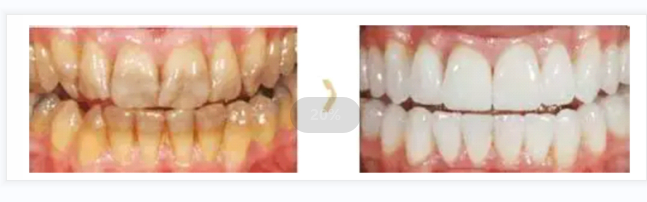

二.全瓷冠美容修複

全瓷牙是指由瓷材料制作(zuò)的人工(gōng)牙冠。其有(yǒu)着最佳的美學(xué)特性以及較好的生物(wù)兼容性,尤其适用(yòng)于患者欲改善牙齒的外觀、顔色等情況。

适用(yòng)範圍:牙冠變色、四環素牙、牙體(tǐ)折斷、缺損、牙列缺損(牙齒缺失)、不宜矯正的畸形牙、牙列不齊、牙列缺損的固定修複體(tǐ)、大面積充填後的牙齒等。